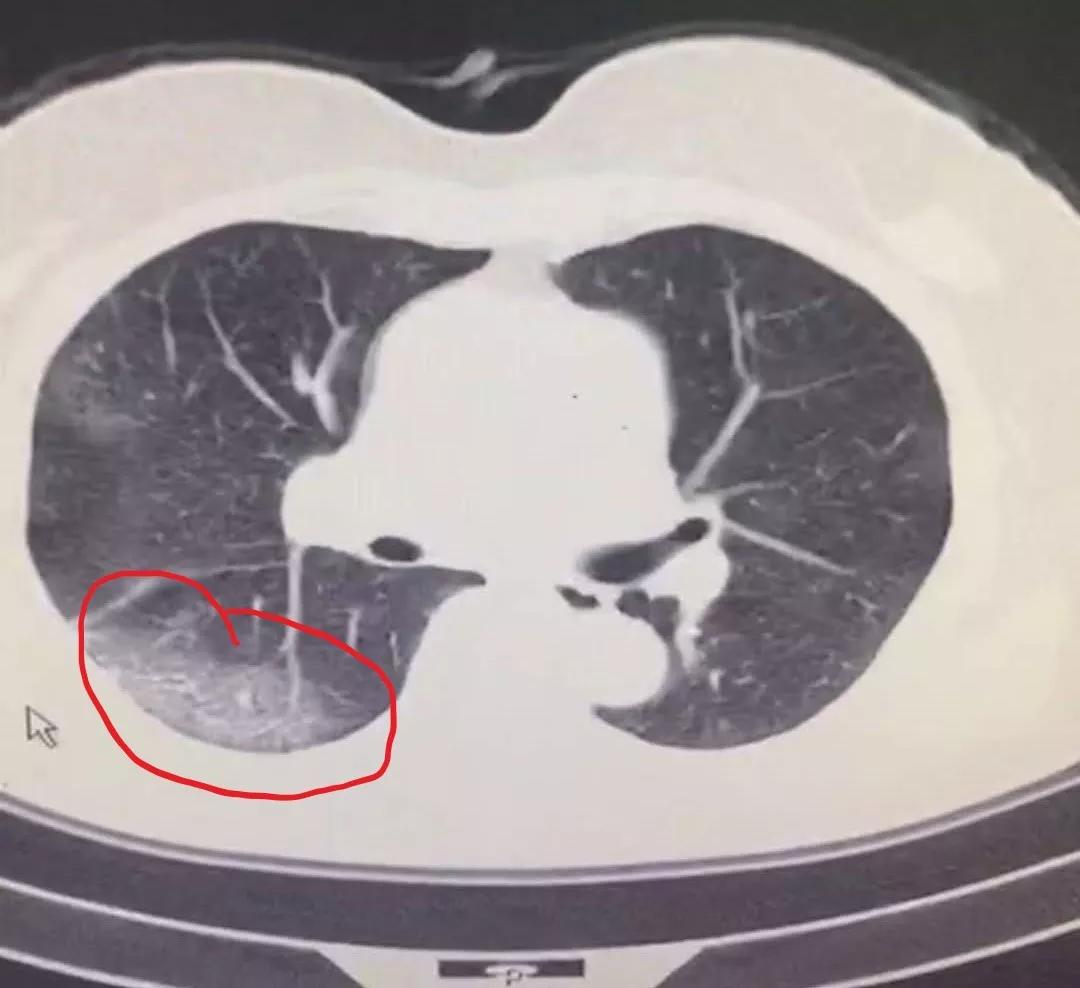

推测病毒感染后,机体出现了强免疫反应,巨噬细胞等免疫细胞吞噬病毒结合细胞(II型肺泡上皮细胞),造成严重肺损伤,这也与肺CT表现相符,感染一般为肺的外带、末梢、肺泡部位(图1。新冠病毒CT表现)。如果是RAS系统反射激活导致肺损伤,应该是肺的整体、多段损伤,而不是局部(图2.SARS肺炎CT表现)。

(图1、新冠病毒肺炎CT表现)